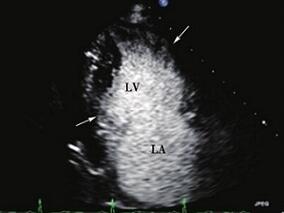

1小时条评论病例摘要(先证者) 男性,48岁。主因发作性心悸、气促、胸闷、上腹胀1年,再发1个月于2008年6月30日入院。 现病史 患者于1年前无明显诱因出现心悸、气促、胸闷、伴腹胀,胸闷位于心前区,持续约数分钟。间断性住院治疗 (具体不详),症状可缓解。10个月前,患者于外院行24...